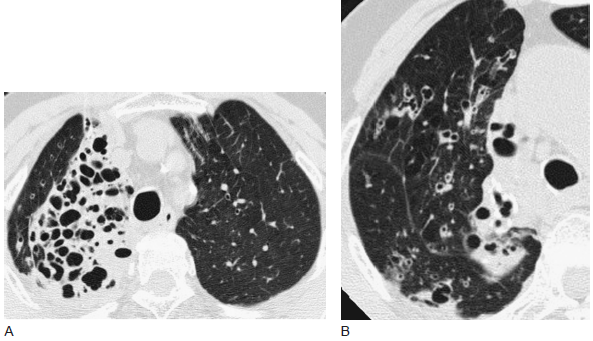

CT 区分支气管扩张的原因_CT_支气管扩张

316x231 - 67KB - PNG